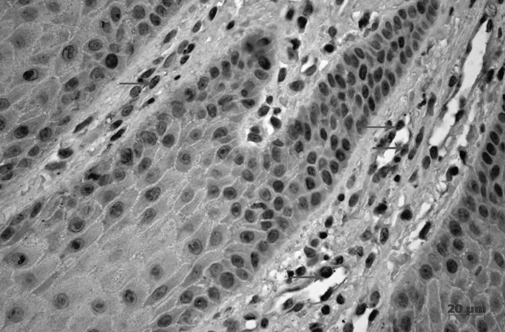

По данным иммуногистохимических исследований биоптатов десны с клинически диагностированным хроническим генерализованным катаральным гингивитом только эпителиоциты базального слоя были PCNA-положительные (рис. 1). Известно, что PCNA экспрессируется клетками, находящимися в S-фазе клеточного цикла и свидетельствует об их интенсивном размножении [5]. Также известно, что ядерный антиген пролиферирующих клеток (PCNA) в интерфазных ядрах встречается при репаративном синтезе ДНК после повреждения клеток [6, 7]. Наличие антигена PCNA только в клетках базального слоя указывает о сохранении адекватной физиологической функции эпителия.

Рис. 1. Хронический генерализованный катаральный гингивит. Экспрессия PCNA клетками базального слоя. Иммуногистохимическая реакция на PCNA. Докраска гематоксилином.

При иммуногистохимическом исследовании PCNA данный антиген в строме экспрессировался в основном эндотелиальными клетками сосудов, пронизывающих сосочковый слой собственной пластинки (рис. 2). Следовательно, пролиферативная активность клеток внутренней оболочки сосудов свидетельствовала об их новообразовании и являлась признаком компенсаторной реакции при развившейся гипоксии, вызванной микробными агентами [4].

Рис. 2. Хронический генерализованный катаральный гингивит. Экспрессия PCNA эндотелиальными клетками капилляров сосочкового слоя собственной пластинки десны (↑). Иммуногистохимическая реакция на PCNA. Докраска гематоксилином.